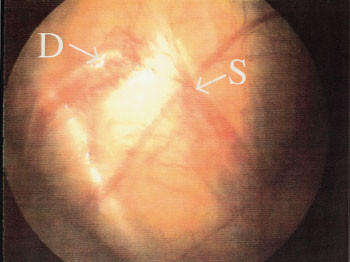

Videre får man identifisert en gruppe pasienter som mangler den aktuelle testikkel, og som derved kan spares for ytterligere kirurgisk inngrep. En mulig årsak til manglende testikkel er prenatal intraabdominal testikkeltorsjon (13). Funn av intraabdominalt blindt endende testikkelblodkar og ductus deferens regnes som en sikker påvisning av manglende testikkel (fig 2). Således unngikk 19 gutter i vårt materiale ytterligere kirurgisk inngrep i tillegg til laparoskopien. Åtte gutter som var primært lyskeeksplorert ved andre sykehus, kunne ha vært spart for dette inngrepet hvis de hadde vært laparoskopert først.

Hvis man ser testikkelen intraabdominalt (fig 3), har man muligheten til å velge den mest hensiktsmessige kirurgiske fremgangsmåte for orkidopeksi, som vil avhenge av om testis befinner seg like innenfor indre lyskering eller lenger proksimalt.